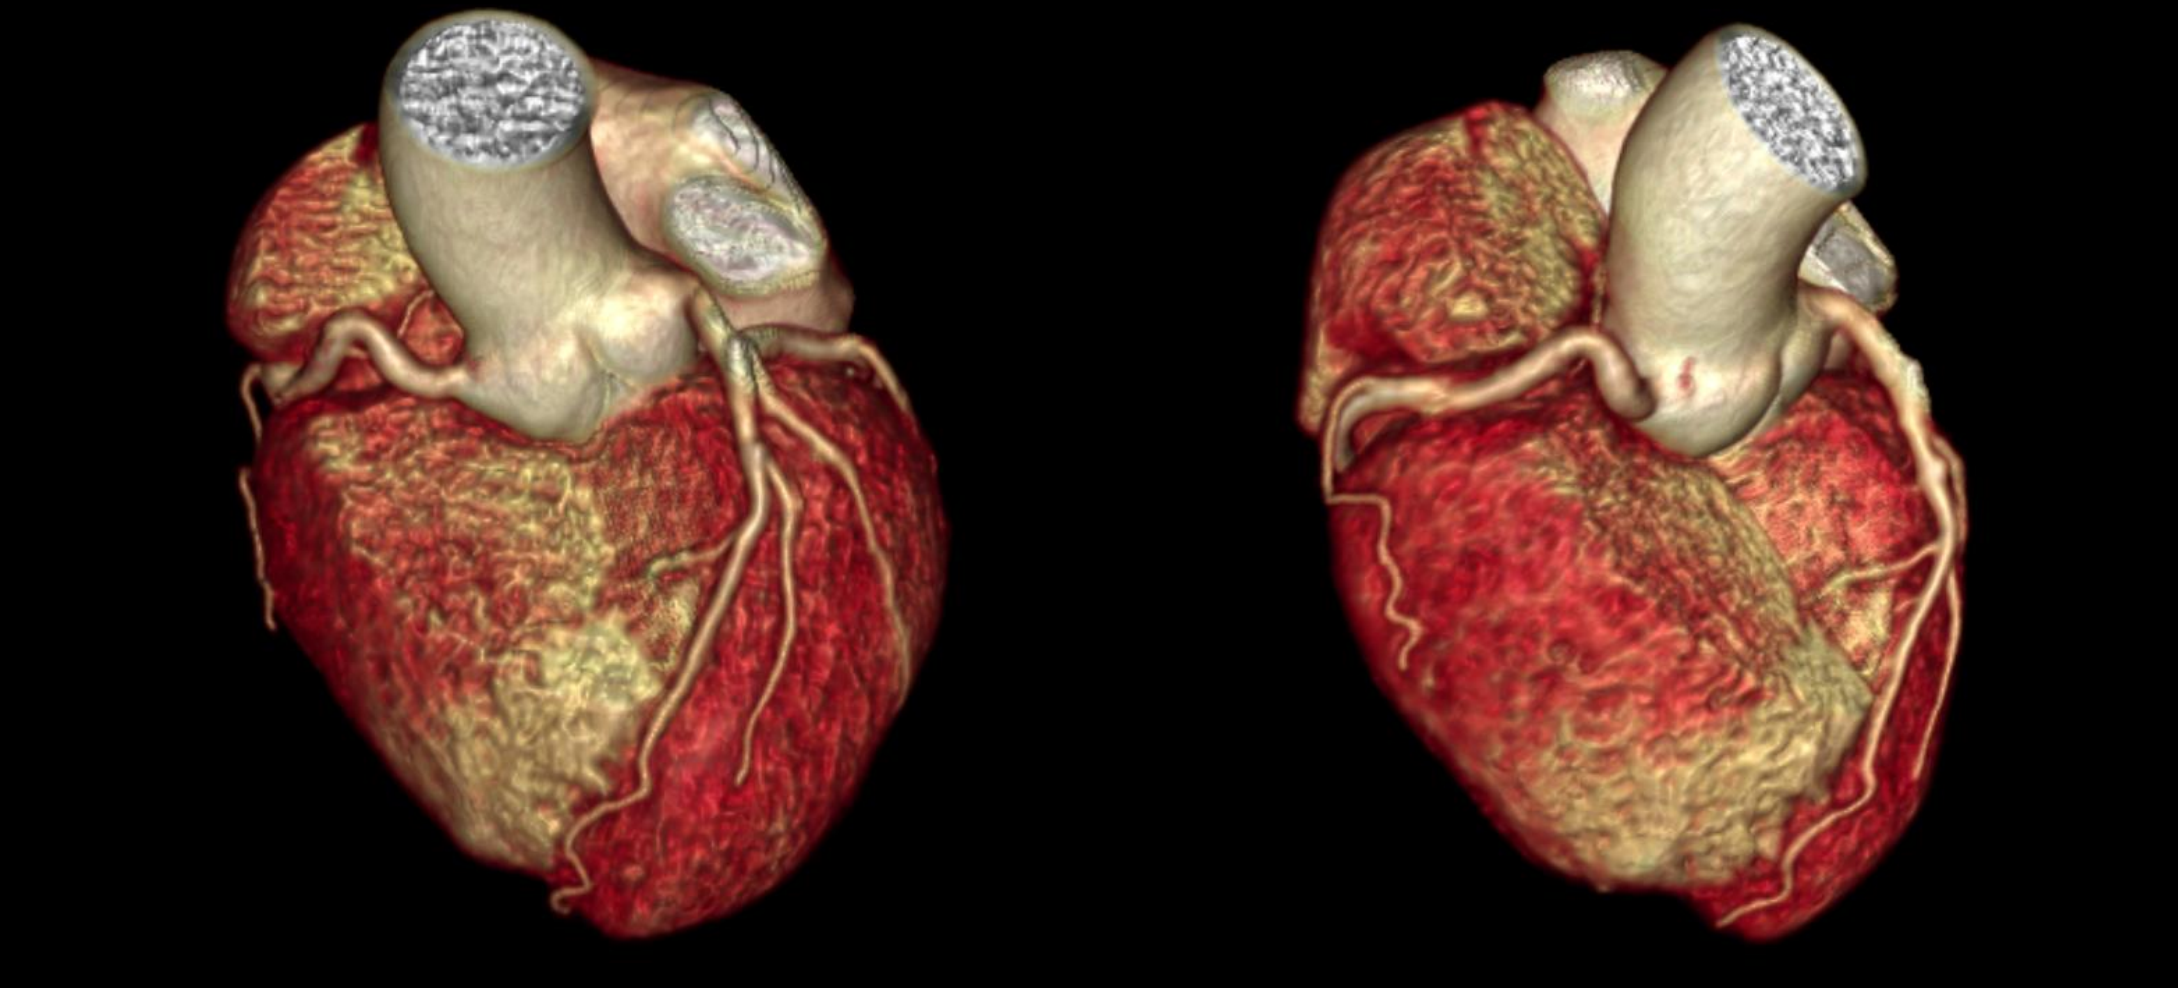

Hệ thống CT tiên tiến này sở hữu tốc độ quay siêu nhanh 0,286 giây, bóng tia X công suất 7,5 MHU (hiệu dụng lên đến 27,1 MHU) cùng detector độ rộng 40 mm. Nhờ các công nghệ hiện đại, hiệu suất chụp tim vượt trội được nâng lên một chuẩn mực mới, mang lại hình ảnh tim mạch chính xác và ổn định. Thiết bị tích hợp nền tảng AI toàn diện, bao phủ toàn bộ quy trình từ định vị bệnh nhân, quét, kiểm soát liều, giảm nhiễu và triệt tiêu artefact đến hậu xử lý hình ảnh và hỗ trợ chẩn đoán, đảm bảo độ chính xác vượt trội ngay cả trong những tình huống lâm sàng phức tạp nhất.